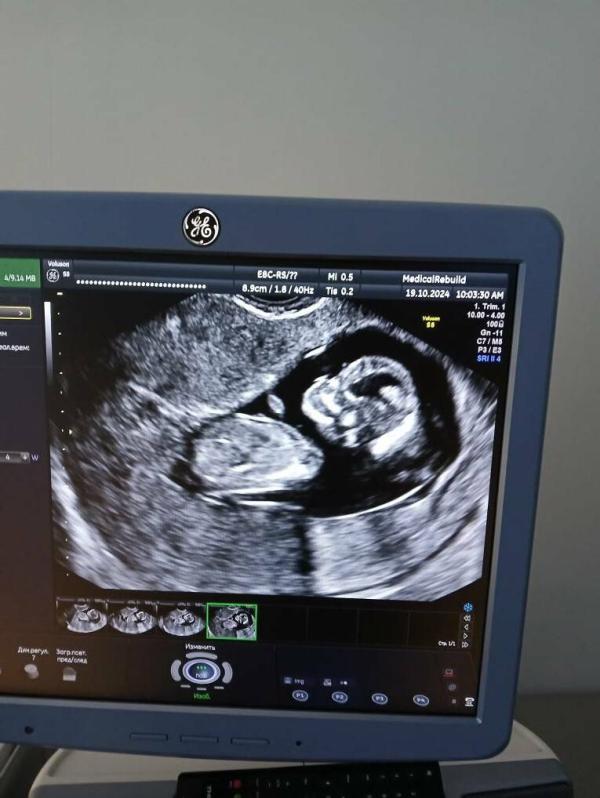

Наша малышка🥰 Привет сегодня передавала

До сих пор не верю,что она наша. Хотя после крови 2 раза в этом убедились🥹